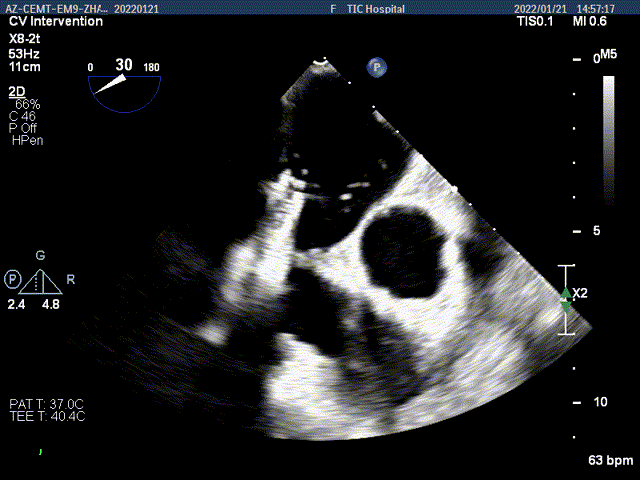

TEE Bicom view:二尖瓣后叶P2区脱垂,宽16.3mm

Color-view:大量反流,主要血流PISA来源于2区

2D视图下判断大鞘位置及长度

2D视图下trajactiory

2D视图下开夹子